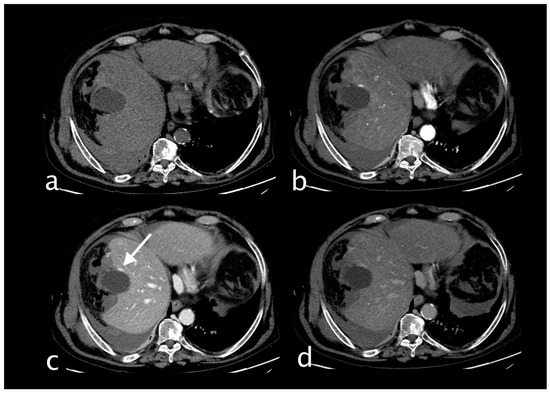

2. Imaging

3.1.3. Imaging and Diagnostic Findings